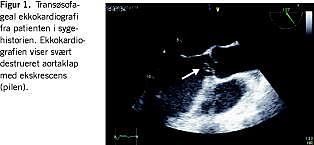

En 60-årig mand, der havde reumatoid artritis og pacemaker, blev indlagt med almen sygdomsfornemmelse gennem flere uger. Patienten var forinden af egen læge sat i behandling med penicillin på mistanke om pneumoni, og han var ved indlæggelsen konfus, rodende og højfebril med en temperatur på 38,6 grader, hypotensiv (blodtryk 90/38 mmHg) og takykard (puls 175/min). Der blev initialt taget et enkelt sæt (en aerob plus en anaerob kolbe) til bloddyrkning før påbegyndelse af antibiotisk behandling med penicillin, gentamicin og metronidazol. Pga. de cerebrale symptomer blev patienten lumbalpunkteret. Lumbalpunkturen viste purulent meningitis med > 6.000 leukocytter, lav glukoseværdi og forhøjet proteinværdi i spinalvæsken. En røntgenundersøgelse af thorax viste højresidig pneumoni. Transtorakal ekkokardiografi (TTE) blev udført, da der var kardial mislyd og lungestase. Man fandt en normal systolisk pumpefunktion med oscillerende ekskrescenser på aortaklappen og svær aortainsufficiens. Ved supplerende transøsofageal ekkokardiografi bekræftede man TTE-fundene (Figur 1). Både bloddyrkning og spinalvæske var uden vækst af bakterier.

Patienten blev akut opereret, og der blev indsat en mekanisk aortaklap. Ved operationen fandt man delvis destruktion og prolaps af højre semilunær flig med en ca. 10 mm. lang ekskrescens. En lignende ekskrescens blev fundet i kommissuren mellem den højre og venstre klapflig. Da der ikke forelå positive bloddyrkninger, blev væv fra den native klap sendt til PCR. DNA blev ekstraheret fra makroskopisk forandret væv, og der blev udført PCR med amplifikation af de første ca. 530 bp af det bakterielle 16 S rRNA-gen. Amplifikationsproduktet blev DNA-sekventeret, og ved sammenligning af basesekvensen med kendte sekvenser i National Center for Biotechnology Information (NCBI) databasen stillede vi diagnosen Streptococcus pneumonia. Rutinemæssig dyrkning og mikroskopi af vævet var negativ. Patienten blev sat i intravenøs behandling med sammenlagt to ugers gentamicin og seks ugers penicillin og kunne udskrives i velbefindende ca. halvanden måned efter indlæggelsen.